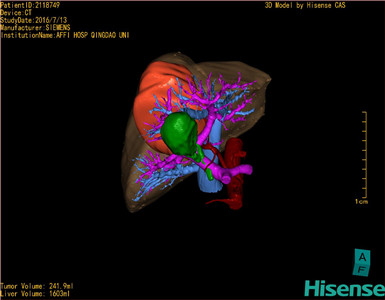

将0.625mm双源薄层CT资料的静脉期和动脉期Dicom格式文件导入海信CAS系统。

通过调节窗宽窗位调整CT序号,对肿瘤,肝实质,胆囊,下腔静脉,肿瘤,肝动脉、门静脉及肝静脉等进行三维重建;系统自动计算肿瘤体积和肝脏体积。

模拟手术操作,自动计算切除肿瘤体积。肝脏体积为1603ml,肿瘤体积为241.9ml,肿瘤体积为肝脏体积的15.1%,通过比对70-80岁正常肝脏体积为1118.08±190.14ml,通过术前模拟手术,精准判断切除后剩余肝脏体积能耐受,避免肝衰竭发生。

术前三维重建:

重建图片